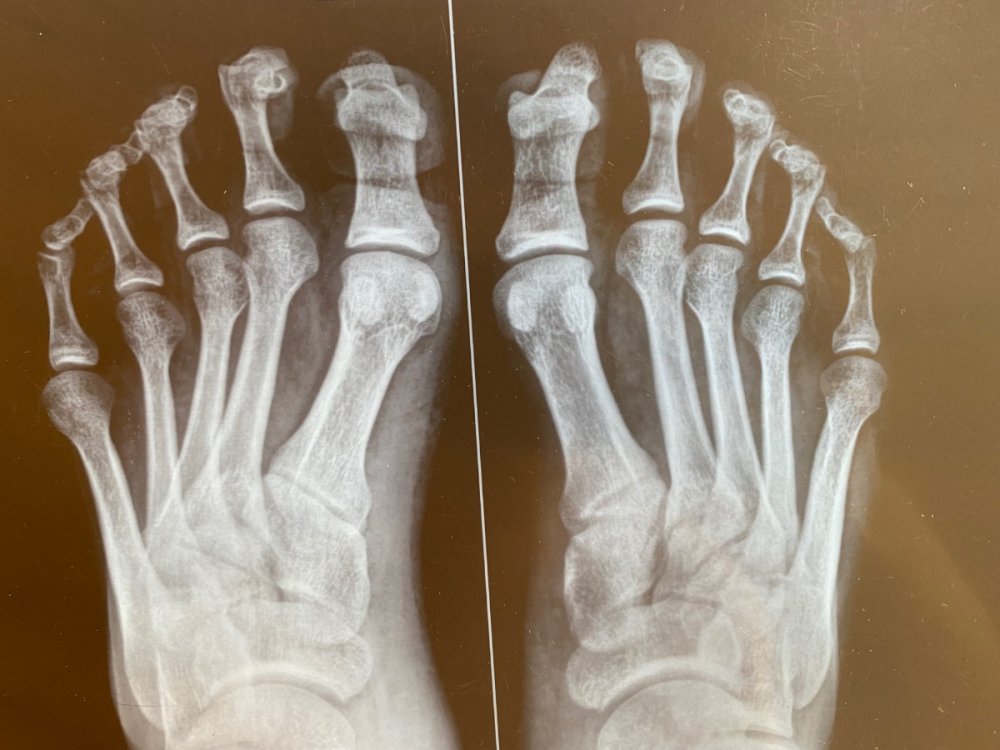

В военкомате направили в областную на подтверждение диагноза. Врач-ортопед выставил следующее заключение: «М20.1 Наружное искривление большого пальца (hallux valgus] (приобретенное)

Вальгусная деформация 1 пальца обеих стоп. Сгибательная контрактура пальцев обеих стоп.». На какую категорию годности я могу расчитывать?